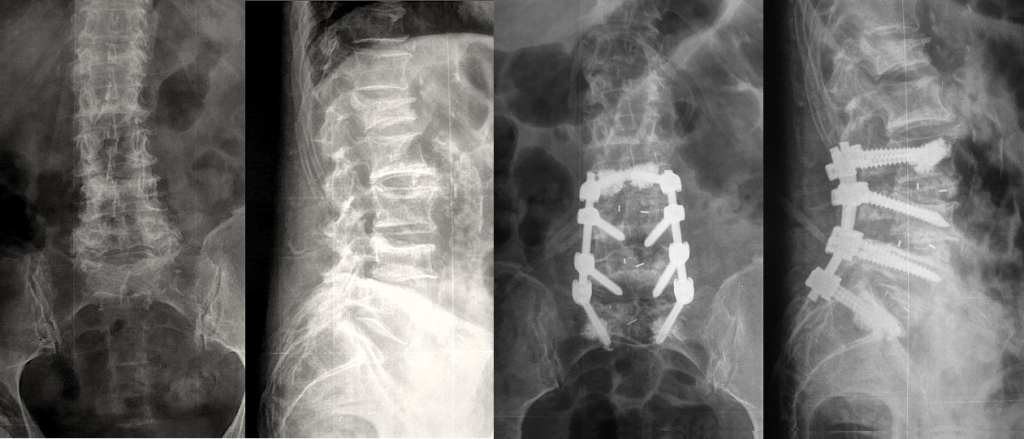

Рентген поясницы: анатомические особенности и медицинские исследования

Раздел: Фотоэссе